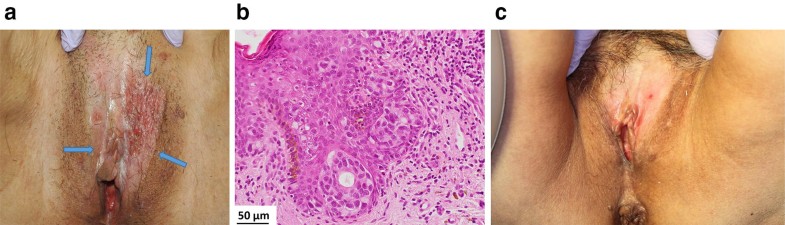

Fig. 5

Macroscopic and pathologic images of a 69-year-old woman with extramammary Paget’s disease (EMPD). a External appearance before boron neutron capture therapy (BNCT): the labia and the vulva, presented as a pinkish, partially depigmented, and eczematous patch with irregular border in the mons pubic area (arrows). b Microscopic findings: pagetoid cells infiltrated all levels of the epidermis and slightly invaded the upper dermis. c External appearance after BNCT: absorbed doses following BNCT were 6.4 Gy-Eq to the normal skin and 20 Gy-Eq to the tumor. The EMPD lesion showed a complete response with depigmentation. She died of heart disease with no evidence of recurrence or adverse effects 3.2 years following BNCT